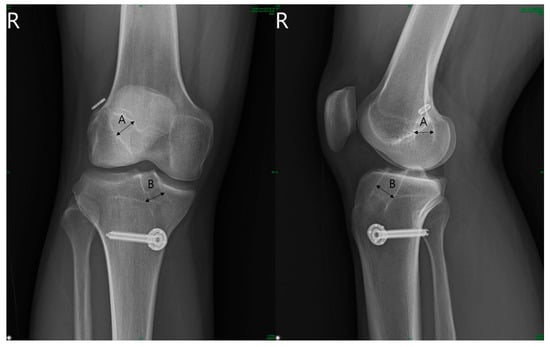

For radiological assessment, standardized anteroposterior (AP) and lateral knee radiographs were taken to evaluate tunnel widening. The diameter of the femoral and tibial tunnels was measured based on the method by L’Insalata et al. []. This involved measuring the length between the inner borders of the sclerotic margins perpendicular to the tunnel axis on the AP and lateral radiographs (Figure 1). Radiographs obtained immediately after the surgery and 2 years postoperatively were used for evaluation.

Figure 1. Tunnel diameter was determined as the widest distance between the sclerotic margins of the tunnel perpendicular to the axis of the tunnel based on the method by L’Insalata et al. The diameters were measured from the AP and lateral radiograph of the operated knee at 2 years post-operation.